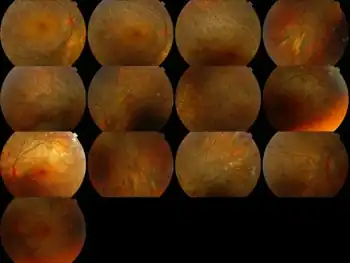

Fundus image of Bietti crystalline corneoretinal dystrophy

In terms of the diagnosis we find that it is based on the clinical findings of typical crystalline deposits (cornea and retina)[8]